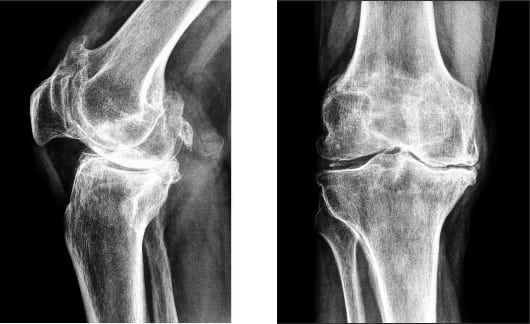

- Гонартроз 1 степени характеризуется повышенной утомляемостью конечности. Кость на этом этапе не претерпевает значительных изменений, однако, едва заметное ограничение движения все же присутствует. Эта степень также характеризуется некоторым сужением суставной щели, которое можно увидеть только на рентгеновском снимке.

- Гонартроз 2 степени сопровождается болевыми ощущениями после нагрузки сустава: во время ходьбы больной слышит хруст в колене. Он не может согнуть или разогнуть сустав полностью. Боль может наблюдаться перед началом движения (стартовая). На снимке заметно сплющивание краев костей.

- Гонартроз 3 степени характерен сильной болью, которая чувствуется, даже если человек находится в состоянии покоя. В пораженной области может возникать отек и повышаться температура. Сустав становится нестабильным, может резко заклинивать.

- Рентгенографию сустава. Тут можно увидеть степень сужения суставной щели, повреждение хряща и кости, наличие скопления солевых отложений, остеофитов.